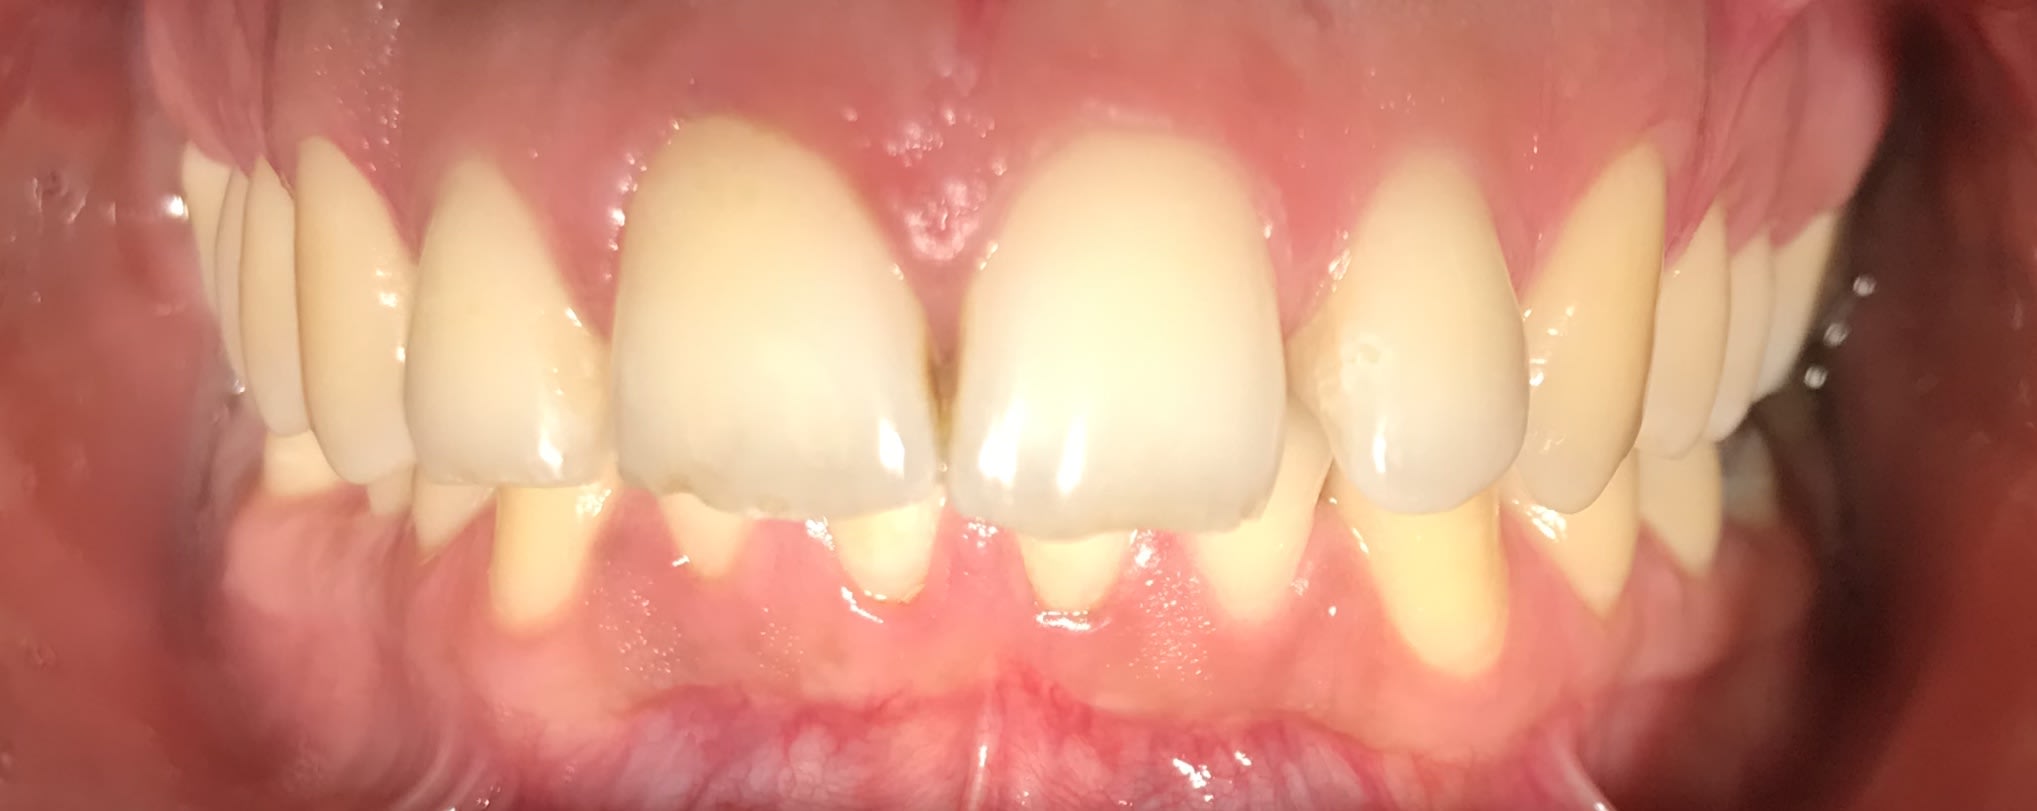

J’ai Algi qui est passé au cabinet avec son problème de classe II . Il a mal à la nuque , et aux temporaux .